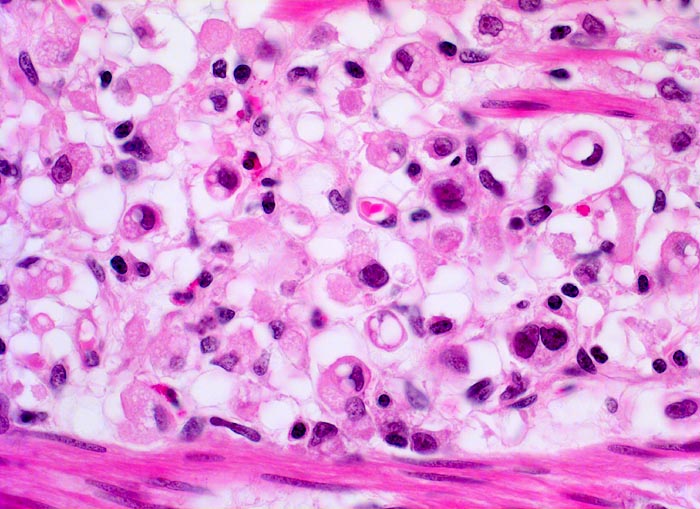

• Ein Grossteil des Tumorinfiltrats besteht aus einzeln oder in kleinen Gruppen liegenden Zellen mit intrazytoplasmatischen Schleimvakuolen, die teilweise den Kern verdrängen (Siegelringzellen): diffuser Typ des Magenkarzinoms nach Lauren.

• Nur vereinzelt Drüsenbildung.

• Lymphgefässeinbrüche.